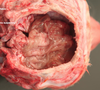

Whats wrong with this cerebrum?

Focal area of discoloration that is causing asymmetry of the cerebrum.

This is a cerebral abcess caused by a tooth puncture in a cat fight

[cryptococcus also causes brain abscesses but will be more protruded]